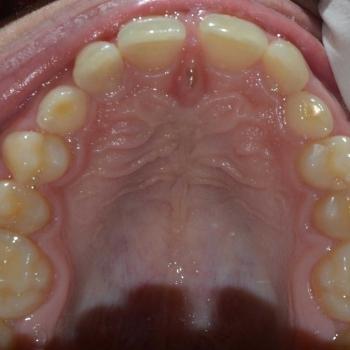

Ádám és édesanyja fogorvosuk javaslatára kerestek fel a felső állcsontban rekedt maradó szemfogak sorbaállításának kérésével. A panoráma röntgenfelvétel elemzése alapján egyértelművé vált, hogy a maradó szemfogak hibás tengelyállása okozta a tej szemfogak perzisztenciáját és a maradó szemfogak előtörésének a hiányát. A szemfogak 30 és 45 fokos dőlésének klinikai képet tovább árnyalták egyéb fogszabályozási eltérések is, mint például a mélyharapás, a nagymetszők közötti rés, illetve jobb oldali második nagyőrlők közötti fordított keresztharapás.

A probléma súlyosságát figyelembe véve, Ádám nagyon bölcsen az önligírozó fém fogszabályozó mellett döntött, melyet bite turbo harapásemelővel és különböző intermaxilláris gumihúzásokkal egészítettünk ki. Az önligírozó fogszabályozó ellenére a kezelés ideje igen hosszú volt. Ennek oka, hogy a szemfogak szájsebészeti feltárása közben derült fény a levontatantó fogak dőlésén kívüli 100-160 fokos tengely körüli elcsavarodására is.